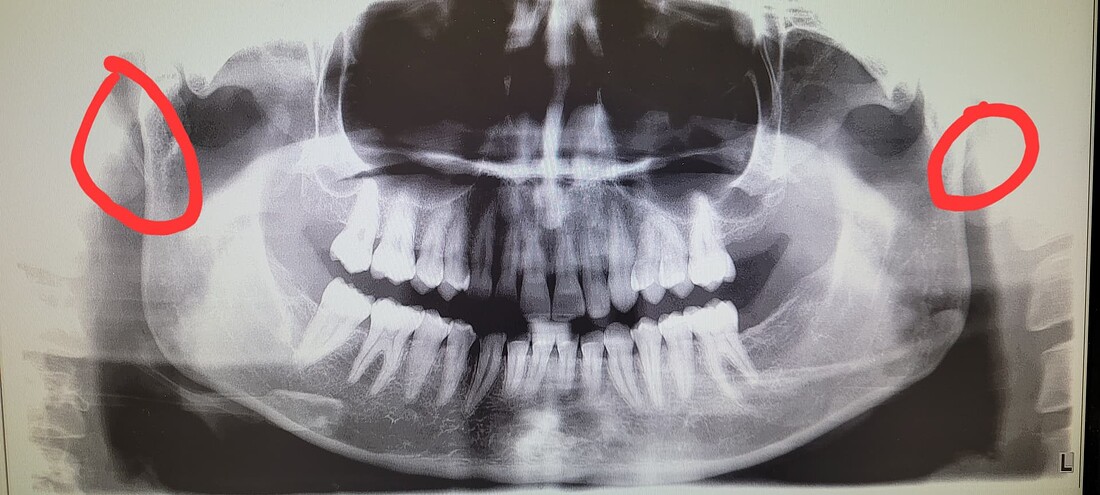

When I was looking at my x-ray and researching straight neck I came across a radiology post on Reddit in which someone had straight neck along with calcified stylohyoid ligaments. I keep looking at my x-ray and honestly I can’t tell if mine is calcified or not. Neck x-ray is from this past week and dental pan is from 2024.

All my issues are on my right side, the grinding in my shoulder/ scapula region, the tinnitus in my ear (constant high pitch not pulsatile), the popping of my TMJ, all on my right side.